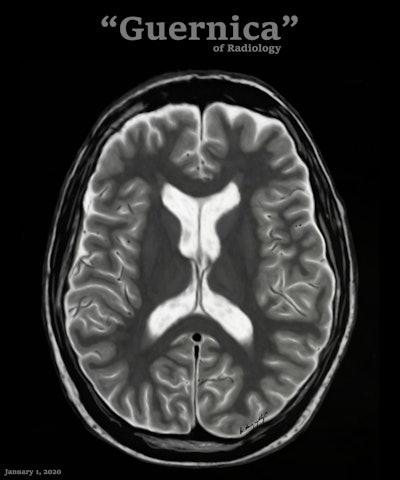

Conceptually, I think it is possible to define the term “radiological illustration” as an emerging discipline that transforms medical imaging data into an aesthetic and didactic narrative. I emphasize that with the motto “pixel by pixel handmade.” I am trying to open a “new path” for the use of visual communication in medical education by trying to combine scientific accuracy in radiological terms with artistic creativity. With this statement, I am trying to express that instead of modifying radiological images, I draw each pixel by hand using technological tools and create a new visual that is both artistically and scientifically original, while remaining faithful to radiological principles.

It’s important to note that radiological illustration should not be confused with medical illustration. The former has yet to be systematically defined in the literature. I believe it deserves recognition as a distinct sub-branch within the broader medical illustration domain.

In September 2025, I had the honor of exhibiting 35 selected illustrations at an international neuroradiology congress in Istanbul, jointly organized by the European Society of Neuroradiology, the American Society of Neuroradiology, and the Turkish Society of Neuroradiology. There were over 1,500 attendees. For the first time, my illustrations were displayed as true works of art under gallery lights and among a crowd. It was an unforgettable experience that left me with deep emotional memories.